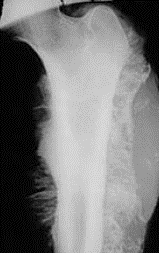

(67 cards)

1

Q

Pathology?

A

Osteoporosis

increased resorption and decreased bone formation; overall organic to mineral matrix balance remains the same, but spicules are smaller, thinner, and more fragile